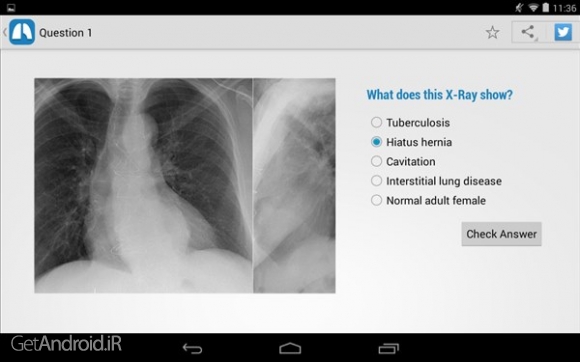

- حل بیش از 100 مورد بالینی

- تحت پوشش داشتن بسیاری از موارد همچون ریه نادر، قلب، استخوان، بافت نرم، وغیره

- وجود بیش از 380 تصویر با كیفیت بالا